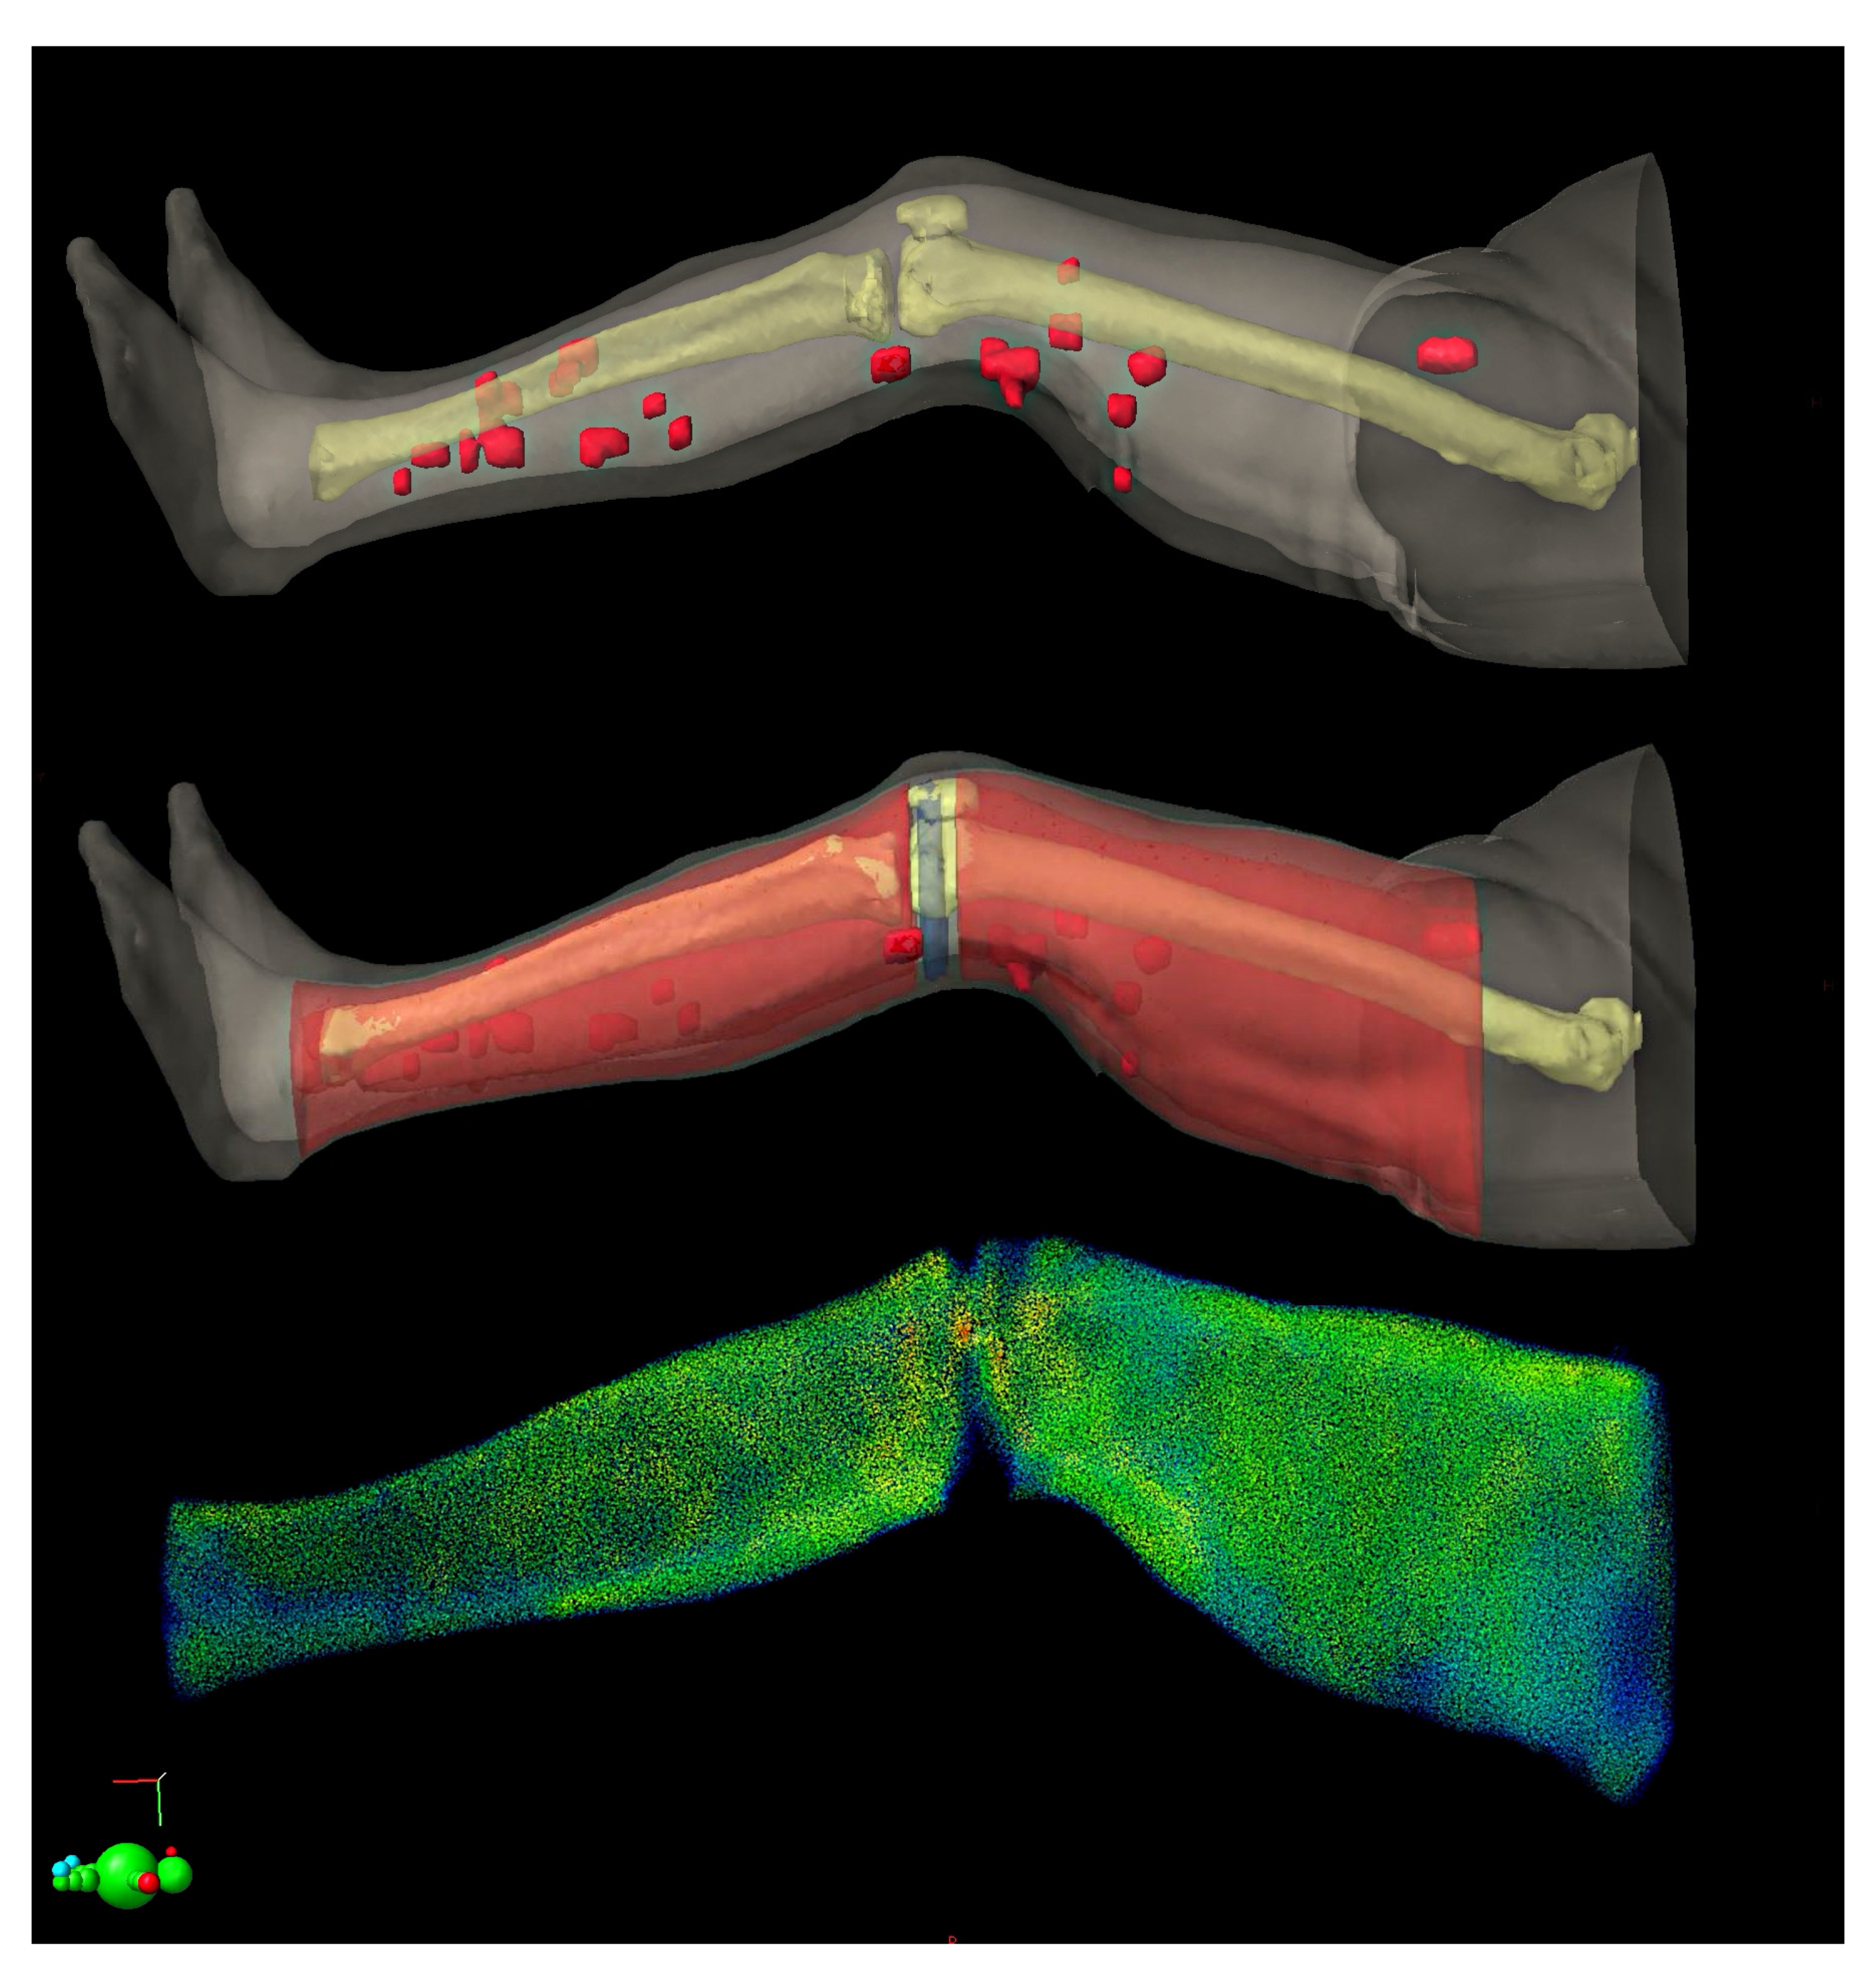

2. Case Study